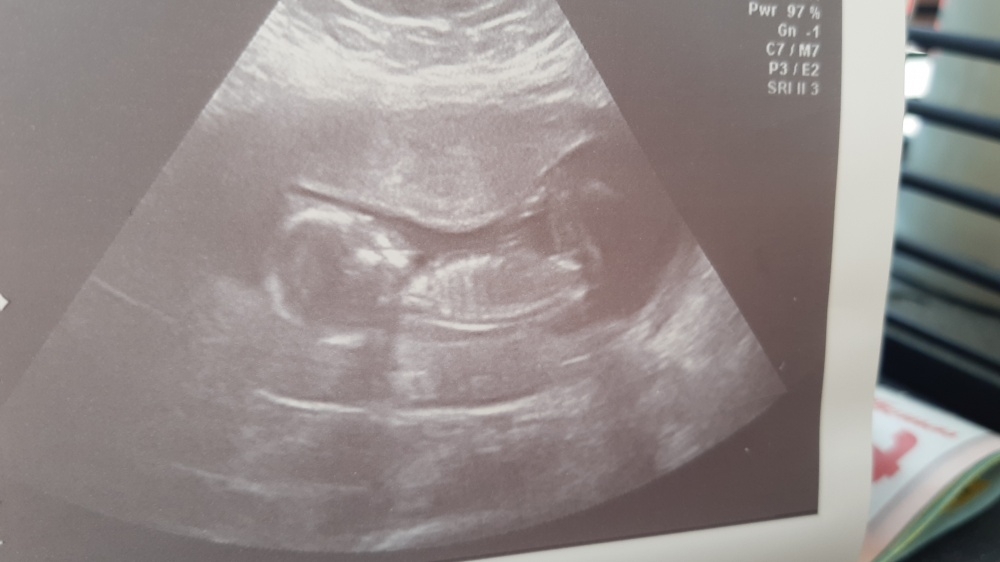

Könnt ihr was erkennen oder diese winkeltheorie ? Liebe grüsse

Von den Bildern würde ich sagen ein Junge, weil der Knubbel nach oben zeigt. Ich hab dazu einen interessanten Artikel gelesen: https://www.24schwanger.de/schwangerschaft/ultraschall-praediagnostik/geschlecht-erkennen/

Vielleicht hilft dir das auch weiter, wenn du die Bilder vergleichst